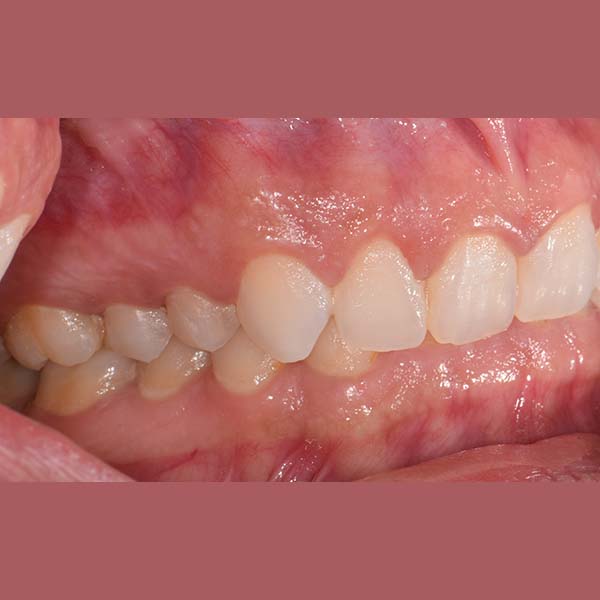

AFTER

Our lady was treated using fixed braces, the tilt in her upper front teeth was adjusted, and the space of their coverage was reduced.

At the end of the treatment, she was able to smile with comfort and confidence again